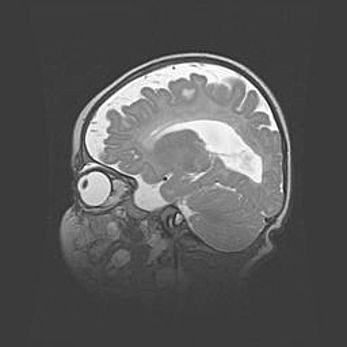

Аномалия Денди-Уокера. Признаки гипоплазии мозолистого тела.

Возраст: 5 месяцев 3 дня

Вес: 5550 г

Пол: мужской

Окружность головы: 39 см

Срок гестации: 40 недель

Аномалия Денди-Уокера – это порок развития головного мозга, для которого характерна триада симптомов: гипотрофия или аплазия червя мозжечка и/или полушарий мозжечка, расширение четвёртого желудочка с формированием ликворной кисты задней черепной ямки, гипертензионная гидроцефалия различной степени.

Гипоплазия мозолистого тела относится к дефектам внутриутробного этапа развития мозговой ткани, возникающим в процессе закладки структур головного мозга, что происходит на начальных этапах развития эмбриона.